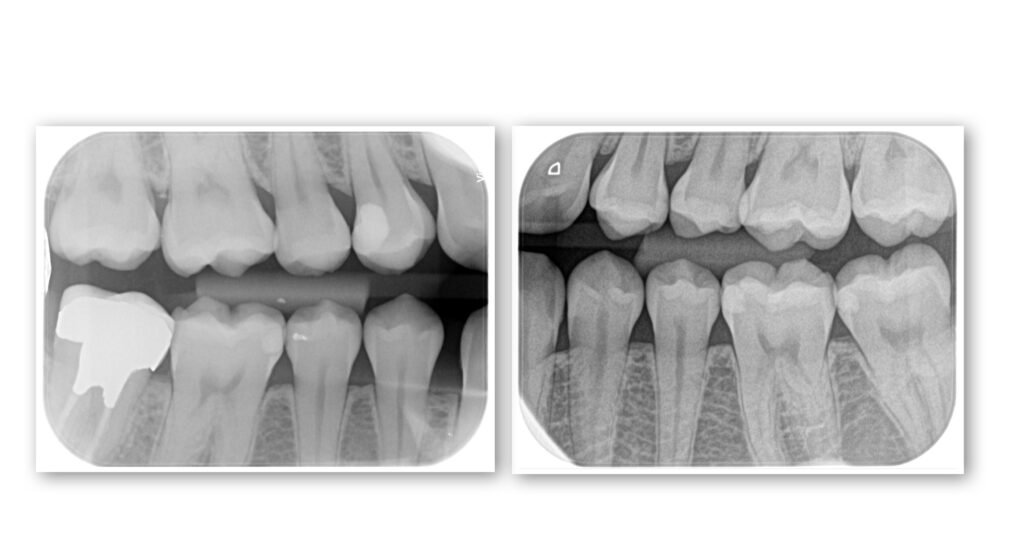

3.レントゲン撮影(2種類)

お口全体のレントゲンと一部を詳しく写すレントゲンの2種類を撮影いたします。

(必要に応じて、追加撮影させていただくこともあります。)

こちらは、見た目ではわからない虫歯や、歯の根っこ、骨の状態などを確認するためには必要な検査になります。